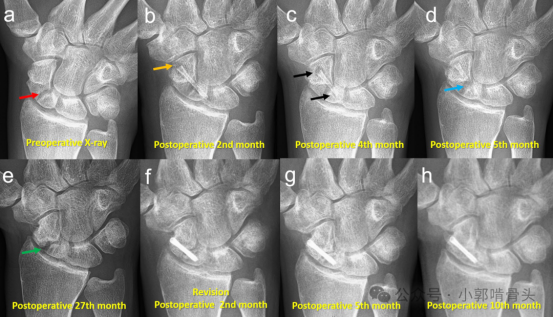

一名患者因舟骨骨折最初采用镁螺钉固定,后因骨不连需翻修手术更换为钛螺钉,其影像学进展如下:(a) 术前X线片:显示舟骨骨折(红色箭头标记)。(b) 术后第2个月:初次固定后的早期X线片,橙色箭头显示螺钉头部周围气体形成。(c) 术后第4个月:持续观察显示骨折部位未愈合及螺钉松动(黑色箭头标记)。(d) 术后第5个月:骨折线持续存在,无愈合迹象(蓝色箭头标记)。(e) 术后第27个月:舟骨骨折仍为骨不连状态(绿色箭头标记),同时螺钉出现吸收现象。(f) 翻修术后第2个月:钛螺钉固定后的X线片。(g) 翻修术后第5个月:显示延迟愈合征象。(h) 翻修术后第10个月:随访显示骨折逐渐愈合,钛螺钉位置稳定。